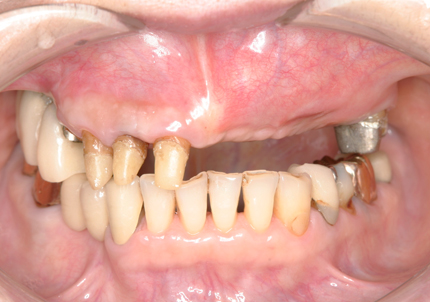

患 者 : E.Y様 女性

主 訴 : 脊髄カリエスの既往により右側上顎欠損、インプラント再治療を含む全顎的な治療希望する

初診日 : 2006年4月24日

既往歴 : 20年前、他院にてバイオセラムインプラント埋入、不良補綴となる

1.初診時(2006年5月)